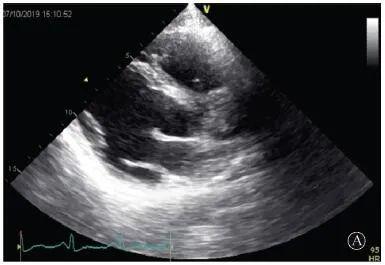

患者入院后無特殊不適,心率70次/min,血壓110/60 mmHg,心功能Ⅱ級。查血常規(guī):血紅蛋白139 g/L,白細胞7.39×109/L,血小板221×109/L。尿常規(guī)、便常規(guī)+潛血均正常。生化:丙氨酸氨基轉(zhuǎn)移酶38 U/L,白蛋白47 g/L,鉀3.9 mmol/L,肌酐(酶法)65 μmol/L,總膽固醇3.52 mmol/L,低密度脂蛋白膽固醇2.08 mmol/L。CK:1256→487 U/L,CK-MB 9.7→3.8 μg/L,cTnI 85.90→68.50 pg/ml。N末端B型利鈉肽原70 pg/ml。CK同工酶電泳:肌酸激酶MM質(zhì)量100.0%(此時CK-MB已正常)。血沉1 mm/第1小時,高敏C反應(yīng)蛋白1.61 mg/L;補體:C3 0.876 g/L,C4 0.174 g/L。免疫球蛋白:IgG 9.52 g/L,IgA 1.73 g/L,IgM 0.62 g/L。血清蛋白電泳未見M蛋白。糖化血紅蛋白5.1%。乳酸(運動前)1.1 mmol/L,乳酸(運動中)6.6 mmol/L,乳酸(運動后)7.8 mmol/L。肌炎抗體譜:抗PM-SCL75(+),余均(-)。心電圖:aVL、V5、V6導聯(lián)T波倒置(圖2)。冠狀動脈CT未見明顯異常。超聲心動圖:左室舒張末內(nèi)徑55 mm,左室收縮功能減低,心尖部、左室壁普遍運動減低,以左室下后壁為著,左室下后壁肌小梁明顯增多可見隱窩,疏松層與致密層之比為1.7;左室射血分數(shù)(雙平面)45%;右冠狀動脈開口6.5 mm,開口處未見明確瘤樣擴張(圖3)。

協(xié)和疑難︱第67例:臨床表現(xiàn)胸痛伴肌酸激酶升高

A:胸骨旁長軸平面,左室舒張末內(nèi)徑略增大,室壁無明顯增厚;

B:胸骨旁左室短軸切面心尖水平,可見心肌肌小梁增多,其內(nèi)可見隱窩(箭頭所示)

圖3 患者入院后超聲心動圖